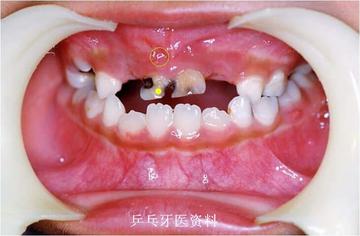

下面这2张图片显示一9岁患儿右上乳牙根尖发炎(黄圈示瘘管),乳牙不掉,恒牙不长,恒牙呈水平阻生

口内照片示:上前乳牙牙根发炎,不能正常脱落

牙片示:乳牙牙根发炎,乳牙滞留,恒牙方向改变,不能萌出